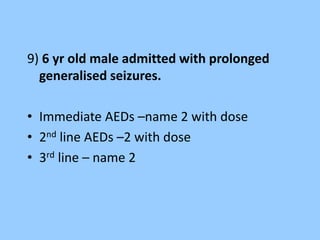

![• Lorazepam [0.05mg/kg],

• Diazepam [0.3mg/kg],

• midazolam[ 0.2mg/kg]

• Phenytoin[ 20mg/kg],

• phenobarb[20/kg]

• Midazolam drip,

• propofol,

• thiopentol](https://image.slidesharecdn.com/eeg-141015043102-conversion-gate01/85/Eeg-in-pediatric-DNB-PEDIATRIC-69-320.jpg)